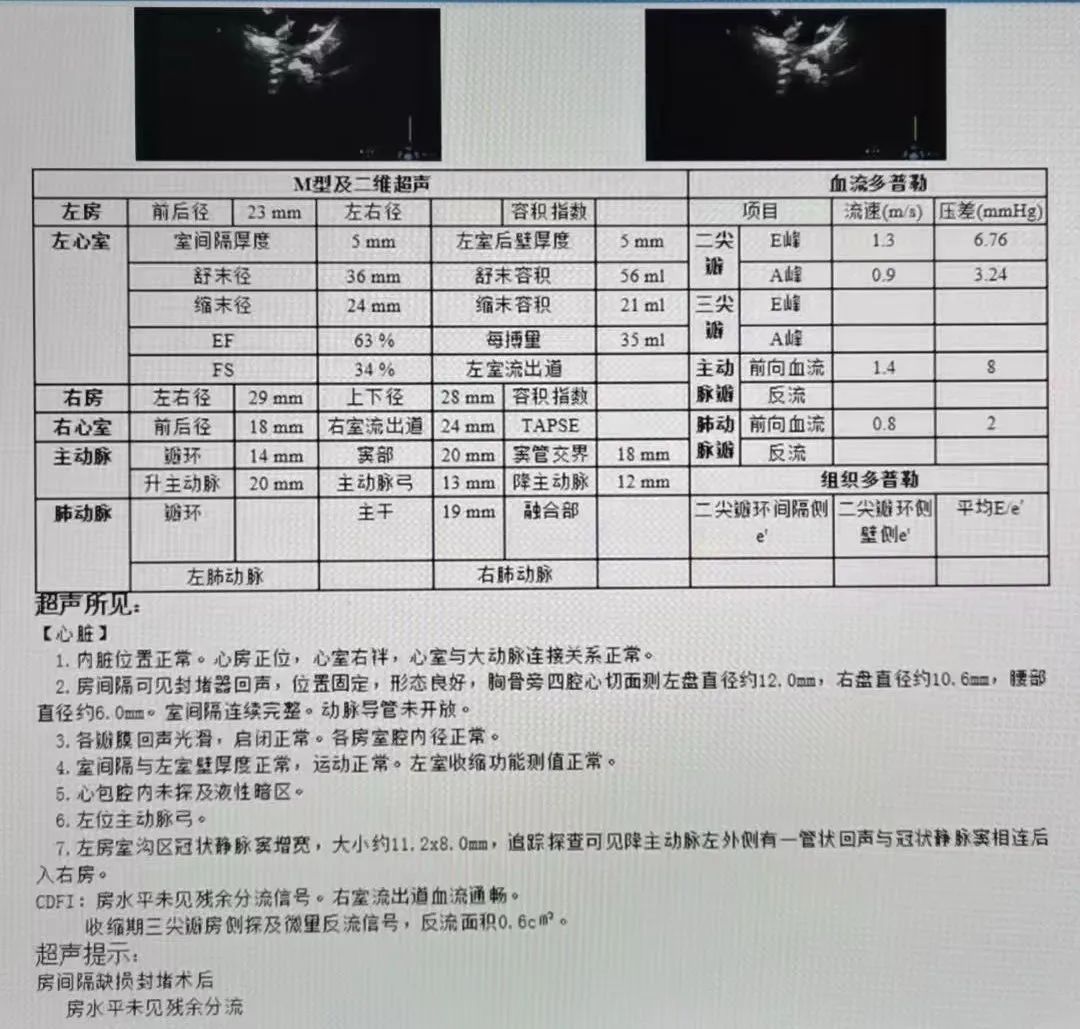

术后六月随访,未见残余分流

超声所见:

1.内脏位置正常。心房正位,心室右袢,心室与大动脉连接关系正常。

2.房间隔可见封堵器回声,位置固定,形态良好,胸骨旁四腔心切面测左盘直径约12.0mm,右盘直径约10.6mm,腰部直径约6.0mm。室间隔连续完整。动脉导管未开放。

3.各瓣膜回声光滑,启闭正常。各房室腔内径正常。

4.室间隔与左室壁厚度正常,运动正常。左室收缩功能测值正常。

5.心包腔内未探及液性暗区。

6.左位主动脉弓。

7.左房室沟区冠状静脉窦增宽,大小约11.2x8.0mm,追踪探查可见降主动脉左外侧有一管状回声与冠状静脉窦相连后入右房。

CDFI:房水平未见残余分流信号。右室流出道血流通畅。收缩期三尖瓣房侧探及微量反流信号,反流面积0.6cm2

超声提示:房间隔缺损封堵术后,房水平未见残余分流。